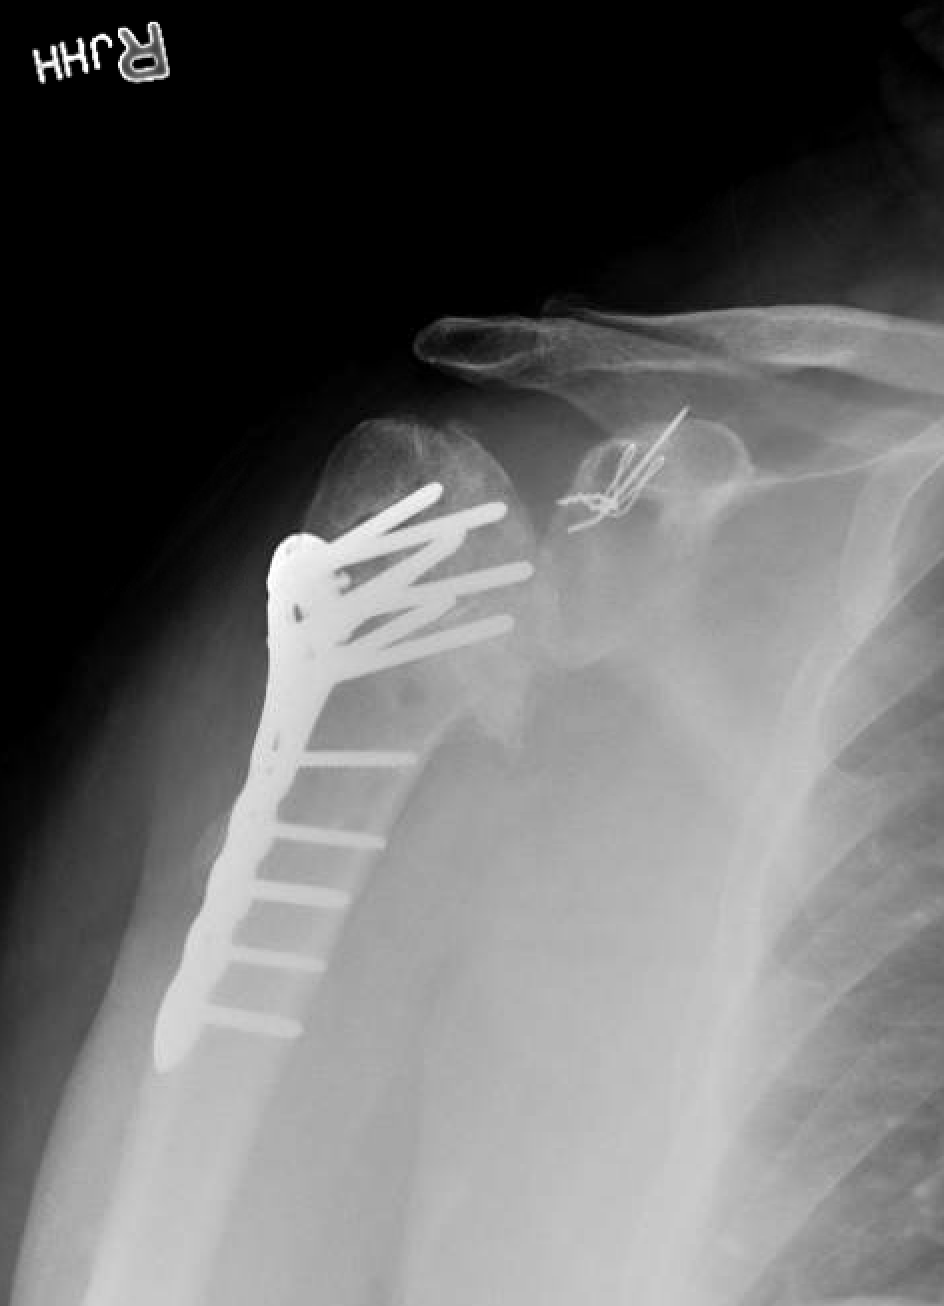

(A, B) Plain radiographs showed the fused elbow with a retained wire Retained Hardware Elbow Icd 10 The assessment of the dictation reads: Removal of hardware can be technically difficult and have it's own associated complications. If the patient is being seen to discuss the hardware removal of a previously well healed fracture without identifiable residual. I'm unsure as what code to use for the retained hardware. Icd 10 code for encounter for removal of internal fixation. Retained Hardware Elbow Icd 10.